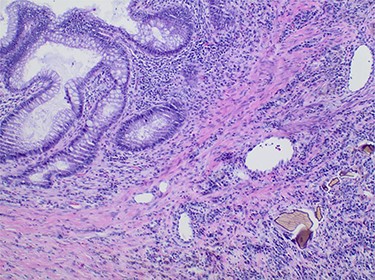

A 65-year-old African American female with history of end-stage renal disease secondary to autosomal dominant polycystic kidney disease presented our Emergency Department with abdominal pain and hematochezia. She was evaluated with esophagogastroduodenoscopy and colonoscopy, which showed multiple non-bleeding sigmoid diverticula and descending colon mucosal erosions consistent with colitis. She was treated medically with metronidazole and ciprofloxacin. Her symptoms recurred 1-week after hospital discharge. She complained of intermittent, severe left lower quadrant pain with associated nausea and non-bilious emesis. Computed tomography (CT) on re-admission showed thickening of the descending-sigmoid colon junction with fluid-filled, dilated colon proximally (Fig. 1). Given symptoms and CT imaging consistent with early large bowel obstruction, the patient was taken to the operating room for exploratory laparotomy, sigmoid colectomy and end colostomy. Surgical pathology revealed pericolonic abscess and Sevelamer crystals (Fig. 2). The patient’s Sevelamer was discontinued, and her postoperative course was uncomplicated. She was seen back for planned elective colostomy reversal 4 months after her initial operation.

Pathology slide of the sigmoid colon with Sevelamer crystals; colonic mucosa (upper left) with adjacent inflammatory reaction containing entrapped sevelamer crystals (lower right).

This case adds to the limited literature on Sevelamer-induced gastrointestinal mucosal injury and obstruction. The first histologic description of Sevelamer crystals in the gastrointestinal tract was published by Swanson et al. They identified non-polarizable ‘fish-scale’ crystals with a yellow–red appearance on hematoxylin and eosin staining. Crystal deposits were associated with mucosal injury, ulceration and inflammatory polyps. The authors suggested a positive correlation between Sevelamer dosing and extent of mucosal injury but were unable to establish direct causation given their small case series [2].